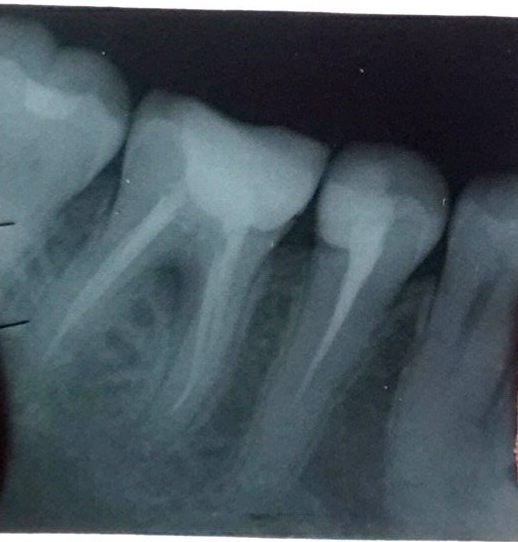

Видела, как после потери пятёрки и шестерки через несколько лет начинает деформироваться лицо...

В основном, советуют имплантацию, но есть варианты с коронками.

Но делать что-то нужно, однозначно. Потом всё становится сложнее и дороже.